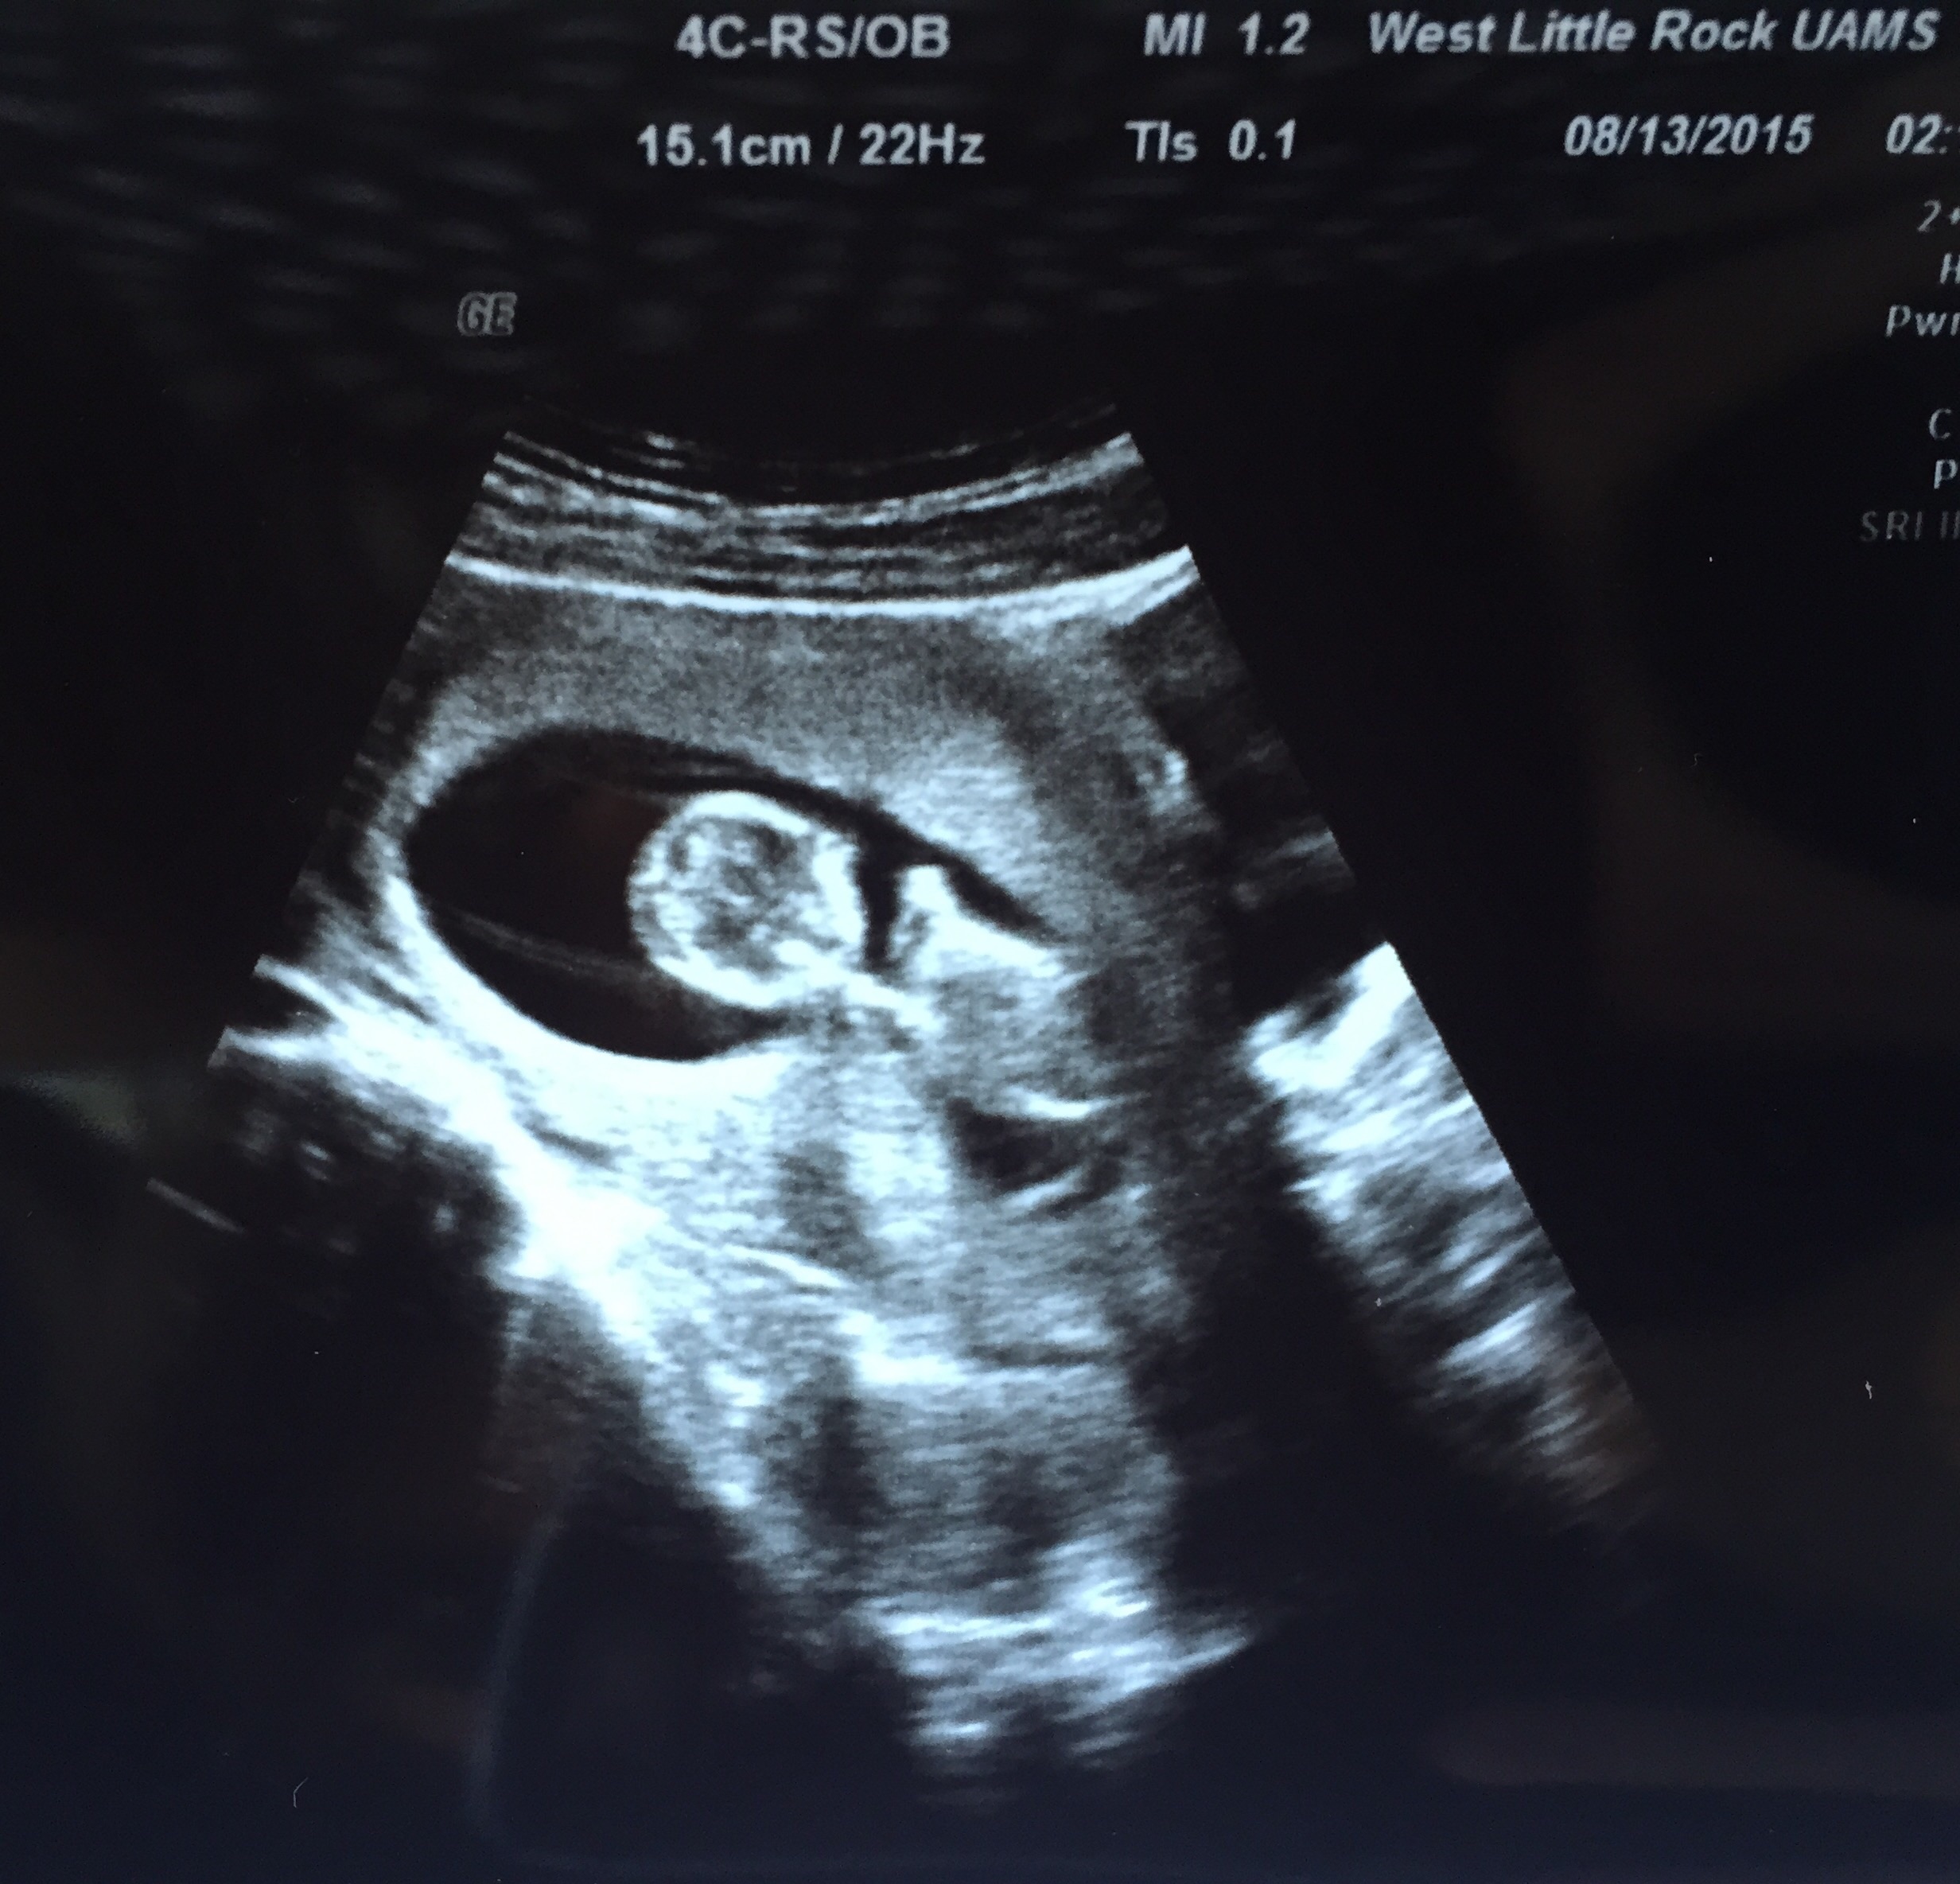

Had our second ultrasound baby was super active and was sucking its thumb ! Heartbeat was 156 Bpm.Ultrasound taken at 12 wks 4 days and today I'm 13 weeks ! Does anyone have a gender guess for my little nugget ? ❤️